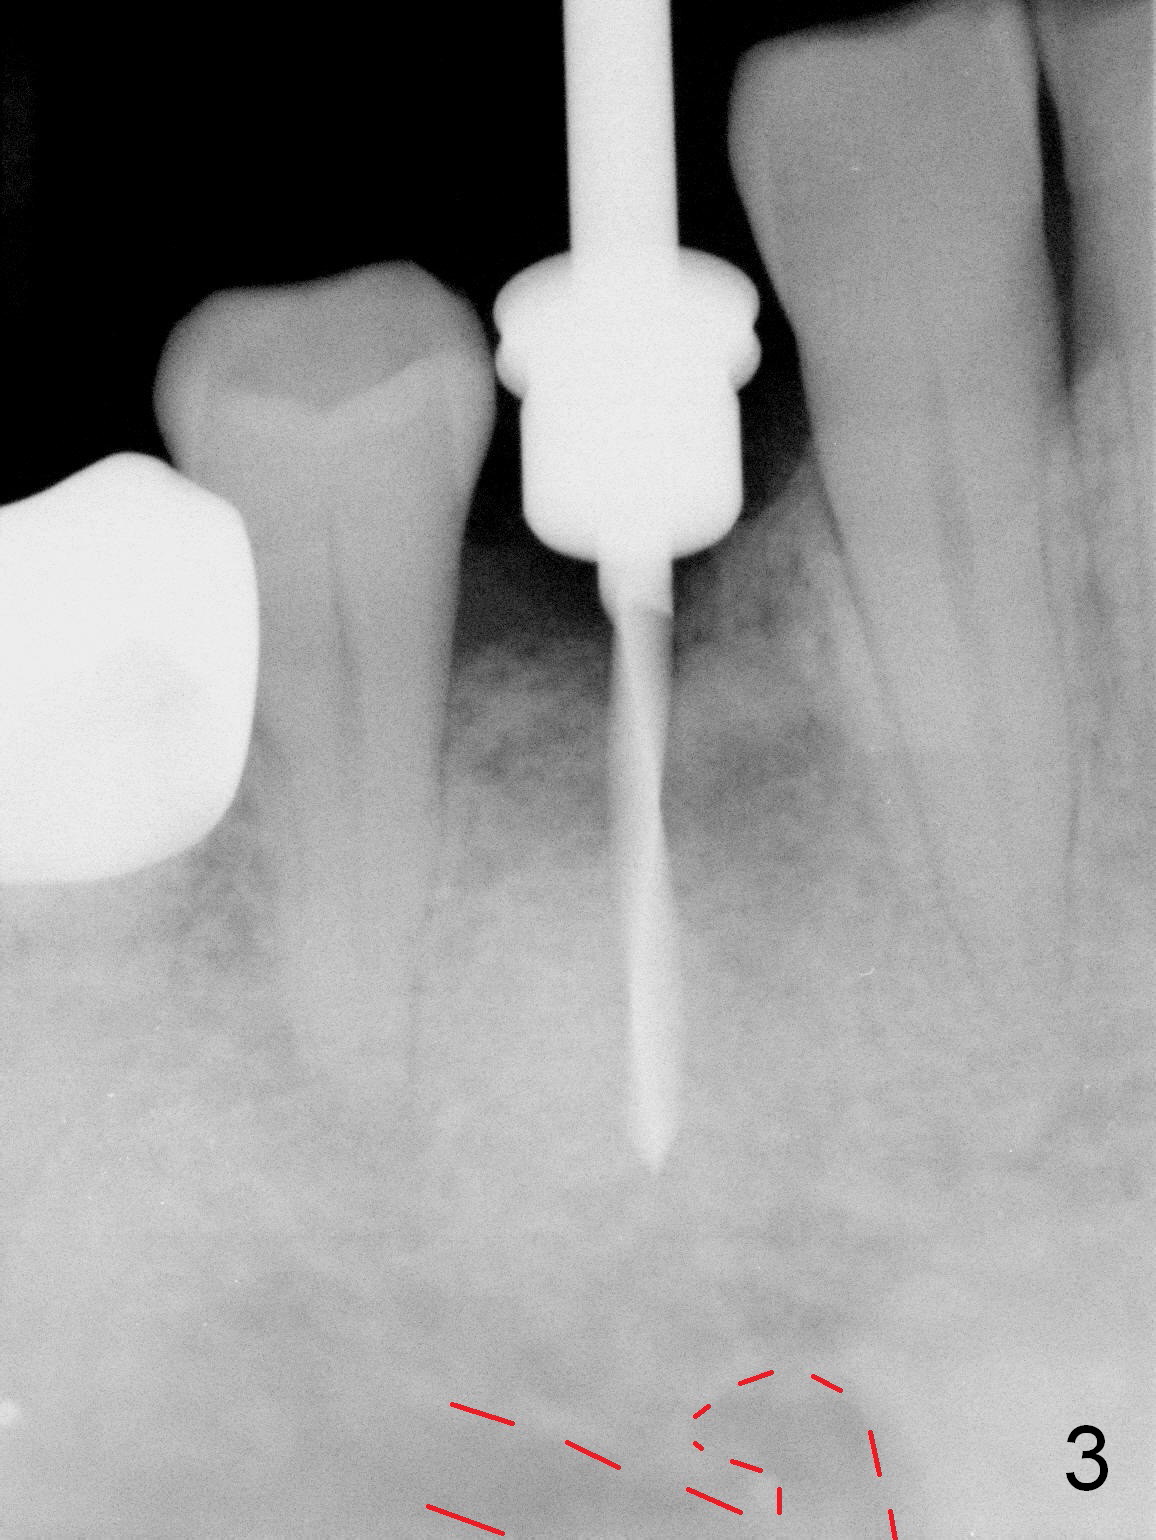

In fact the mesiodistal space of the site of #28 is within normal limit. The buccal plate atrophy is striking (Fig.1) with a fistula (^, associated with underlying residual root tip). When the flaps are raised, the ridge is triangular with the lingual plate (Fig.2 *) higher than the buccal one. Because of the slope, the multiple-drill approach is adopted in stead of single-drill one, because the marking bur is wobbling after 1.6 mm osteotomy at 13 mm (Fig.3). After placement of a 4x11 mm implant, a 4.5x4(2) mm abutment is inserted (Fig.4). The abutment and the implant act as a mesh (framework) so that bone graft and collagen membrane can be laid upon them buccolingually. When the flaps are sutured, there is less tension than that without the abutment. Furthermore, the buccal tissue volume seems to be increased (Fig.5 (<: fistula, which should heal soon), as compared to Fig.1). Tale photos to show effectiveness of the simultaneous GBR and disappearance of the fistula. Three months postop (Fig.6,7 (incomplete abutment seating)), the implant is loaded for intrusion of the opposing supraerupted tooth. The patient returns with chief complaint of food impaction between #27 and 28 three years 7 months post cementation; there is an open contact. Before pick up impression the distal convex surface of #27 is trimmed. The repaired crown has tight proximal contacts before (Fig.9,10) and after (Fig.11) retightening and cementation.